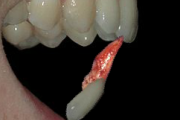

Alveolaarjätke murd